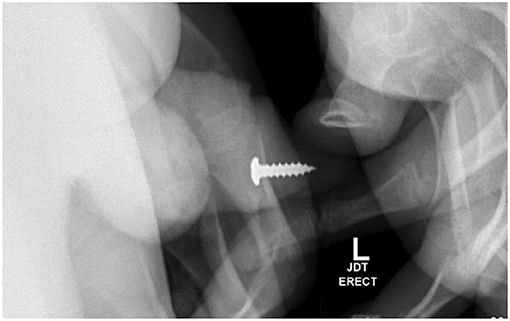

Selama pemeriksaan ini, benda asing teraba di uretra penis distal dan ditemukan benda kedua yakni sekrup. Gejala utamanya berupa retensi urine dan nyeri penis.

Seorang remaja berusia 17 tahun memasukkan sekrup ke dalam uretranya sendiri. Tak hanya sekali, ia memasukkan total 20 kali hingga dilarikan ke UGD. Foto: Adam Bezinque/ jurnal Frontiers In |

Sebuah sekrup ditempatkan di uretra distal dan diposisikan sedemikian rupa, sehingga ujung tumpulnya akan dikeluarkan terlebih dahulu. Tim medis pun melanjutkan penanganan observasional konservatif dengan uji coba berkemih agar pasien dapat mengeluarkan benda asing.